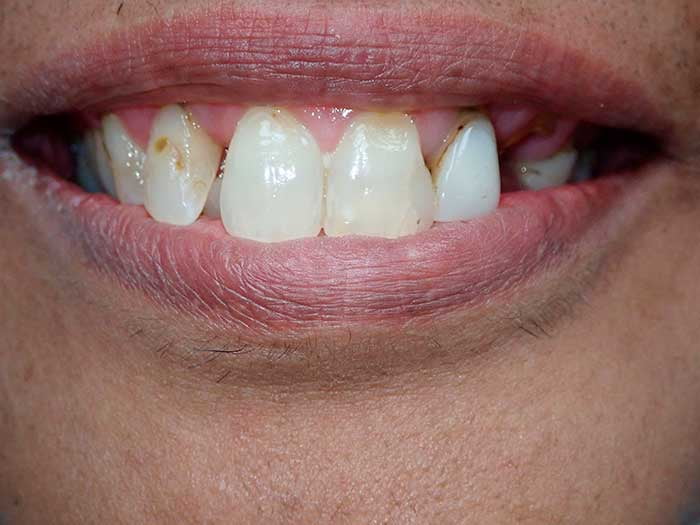

Our Work

Smile Gallery